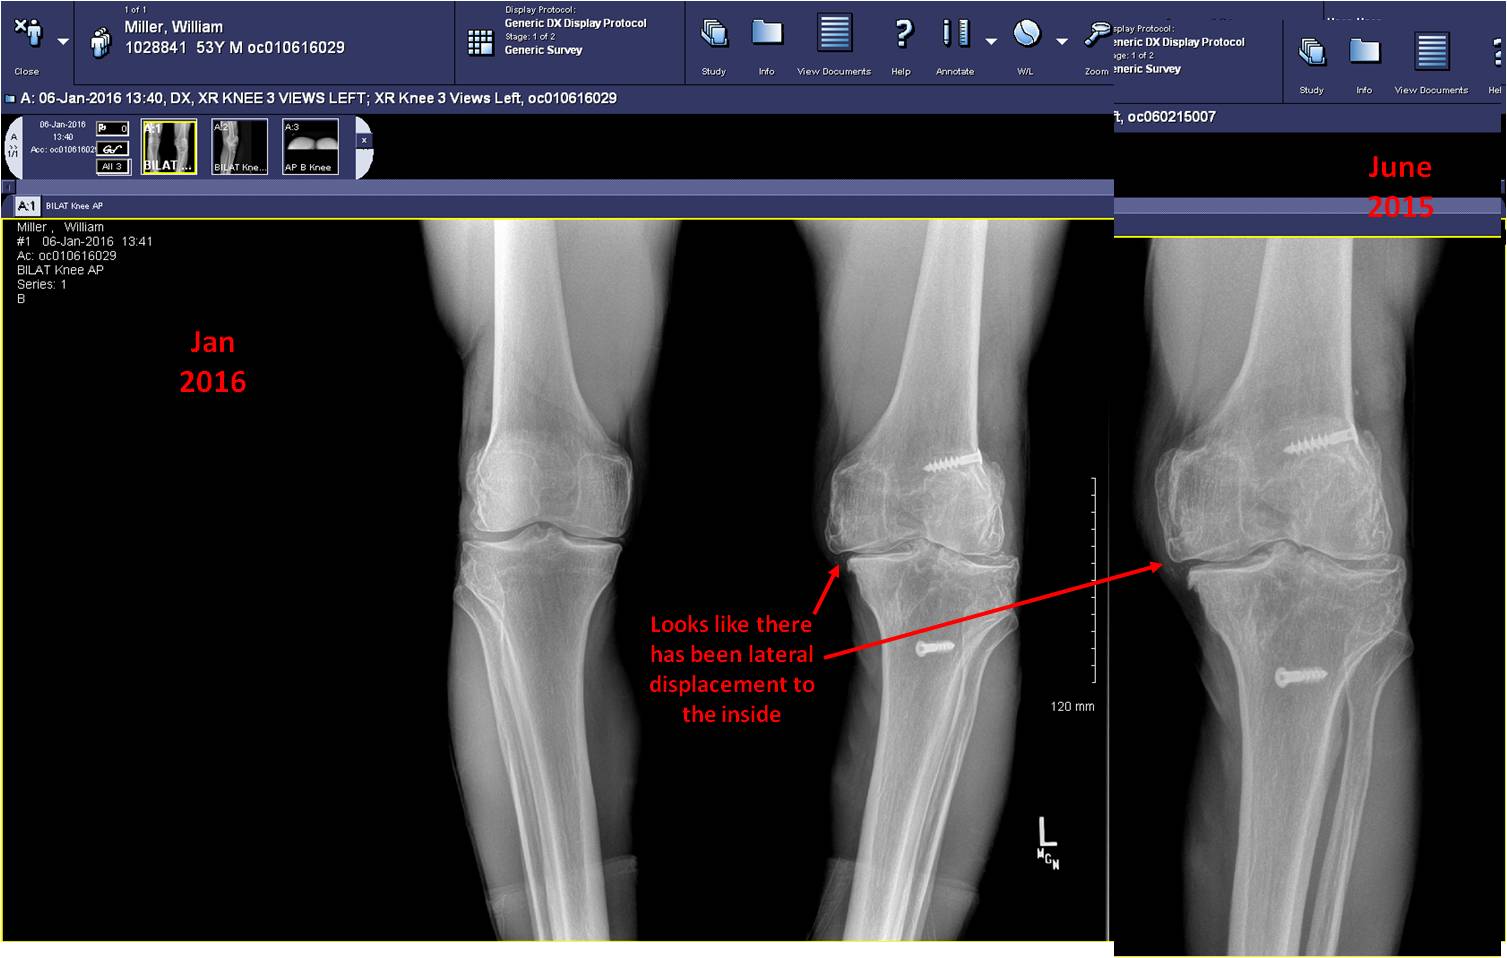

This image of x-rays shows the "good" right knee on the left and 2 x-rays of the "bad" left knee on the right - one from June 2015.... one from January 2016.

What was bad got worse. Looks like the last little bit of cartilage is gone and the knee has displaced even more to the inside.